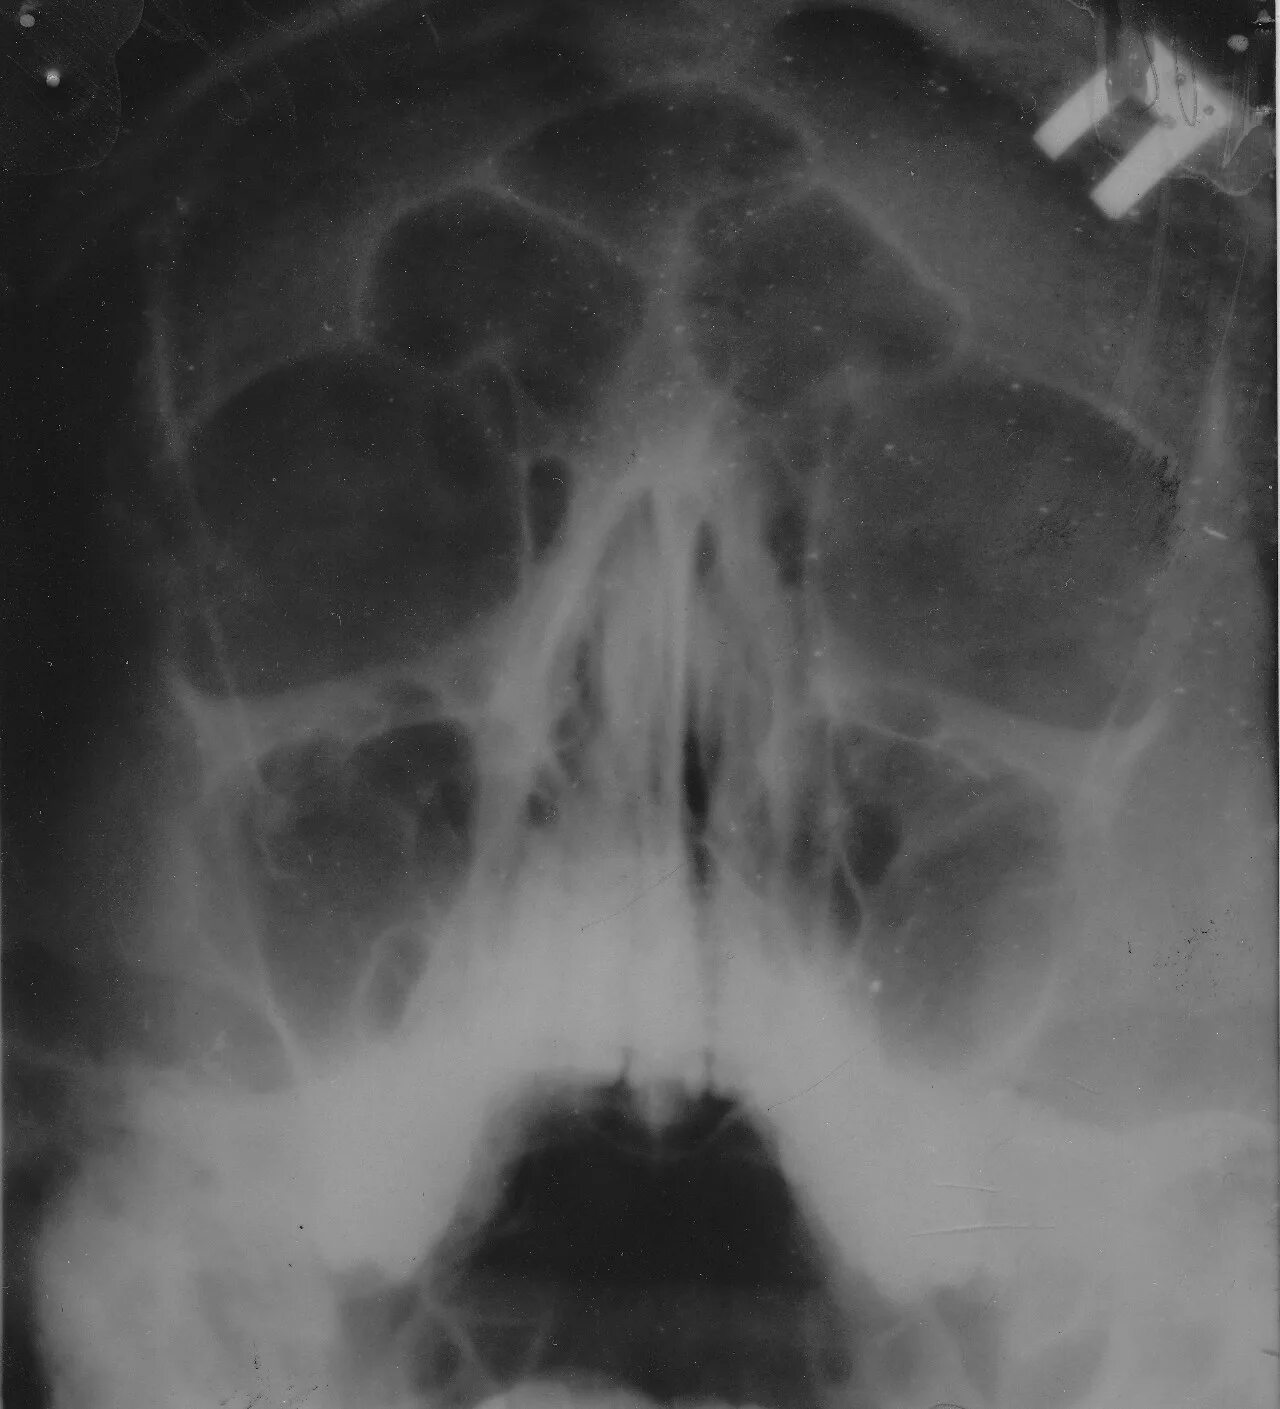

Нарушение пневматизации верхнечелюстных